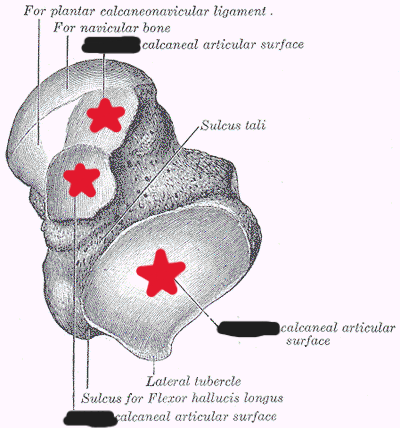

What tarsal(s) does the talus articulate with?

navicular (articulates at the head of the talus)

The trochlear surface of the talus articulates ___, ___, and ___

superiorly with the tibia

laterally with the fibula

inferiorly with the calcaneus

How many articular surfaces does the talus have inferiorly to articulate with the calcaneus?

3 (anterior, middle, posterior)

Label the 3 surfaces of the talus that articulate with the calcaneus